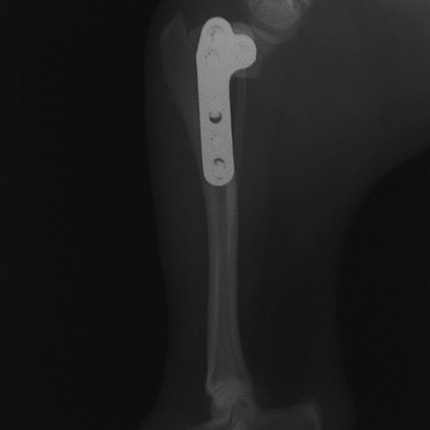

術後左後肢側面像

術後左後肢正面像

術前のTPAは左後肢33.1°右後肢26.8°でしたがTPLO実施により左後肢5.5°右後肢12°に矯正されました。